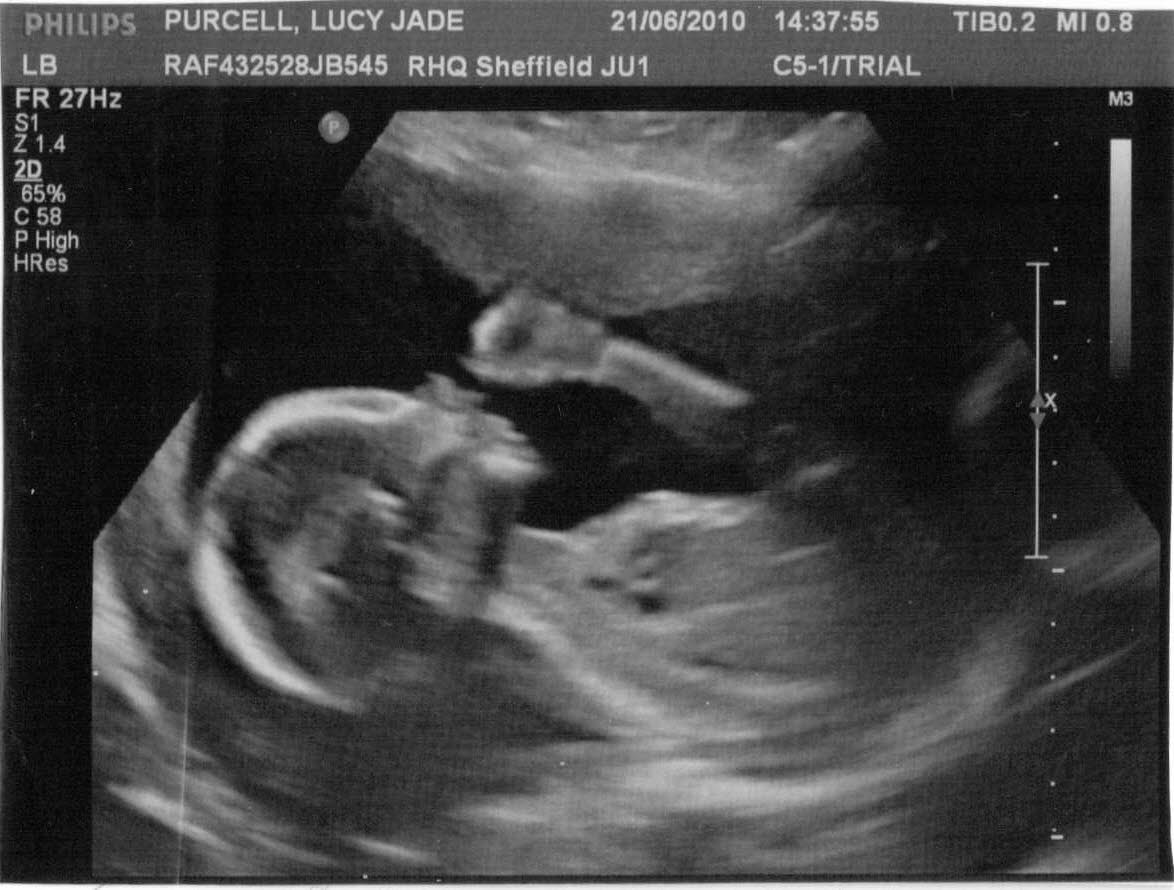

THIS IS ME , THE FIRST BORN OF LUCY PURCELL AND GRAHAM SLACK.

MY NAME IS NOAH.

The two photos below show me in a comfortable position just waiting to come out and see you all. I have had a message from a cousin of mine, called Aliesha, who has told me that this birth thing is no big deal. When the time comes, it's just a matter of crawling along a tunnel and popping out. Although she tells me the exit from this tunnel can be a tight squeeze.